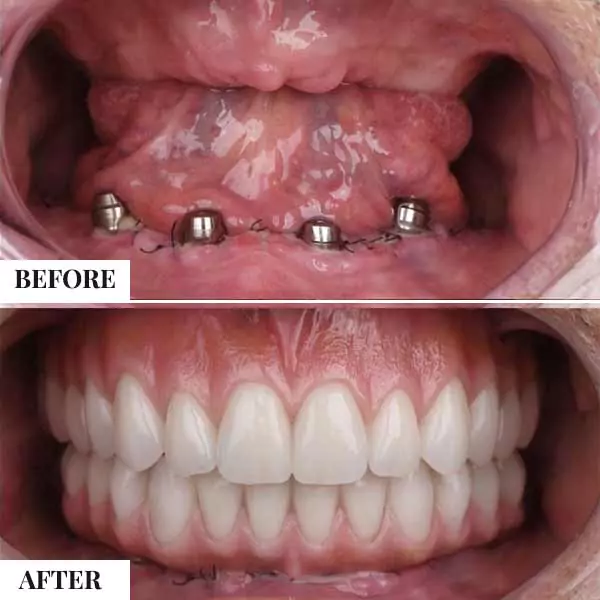

Dental Implants

A dental implant is a root of an artificial tooth. It is fixed into the jawbone and so it can facilitate permanent artificial teeth. Dental implants can support a single artificial tooth or multiple artificial teeth. They are made of dental material like titanium or zirconium. Unlike dentures or other dental restorations like dental bridges, artificial teeth fixed on top of dental implants are closest to natural teeth. They provide superior functionality enabling chewing of food and clear speech. Dental implants are fixed into the jawbone with a dental surgery. Once dental implants are firmly fixed, artificial teeth, dentures, or crowns are placed.